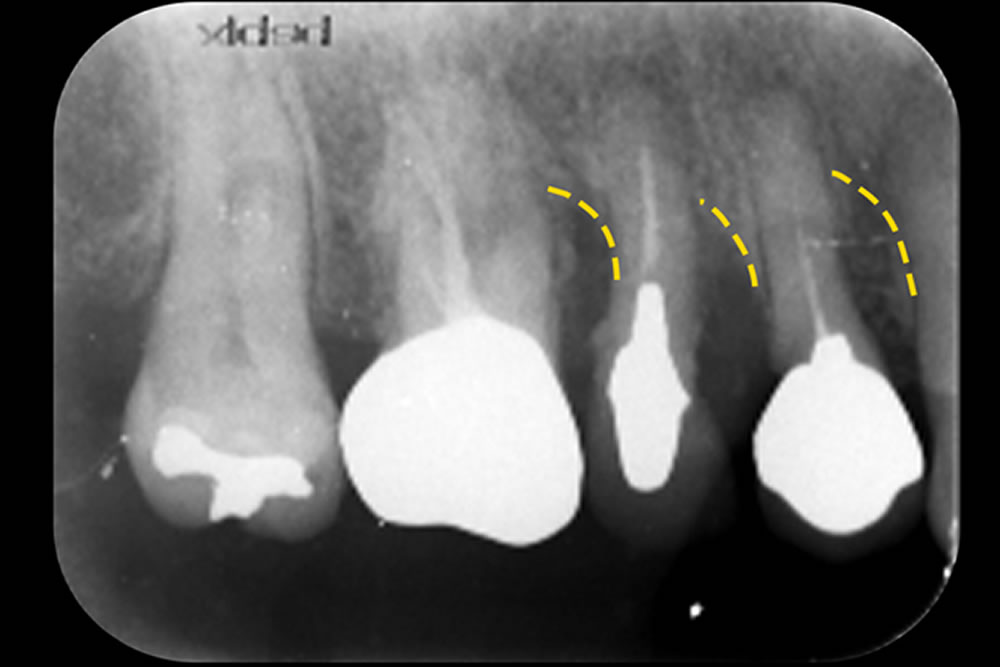

初診時(上写真)、右下6番目の歯は今にも抜け落ちそうな状態でしたが、重度歯周病治療【MINST】によって、症状を改善し、術後1年後(下写真)には歯周組織もしっかりと再生しました。

※外科処置なし・再生材料も使用しておりません。